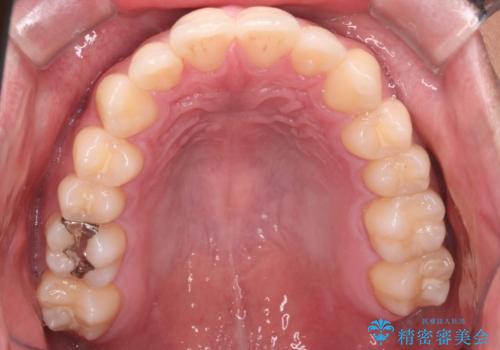

【インビザラインモニター】前歯が出ているのが気になる

- 上の前歯が出ているのが少し気になるとの事で来院されました。

インビザライン希望のため、IPR(歯と歯の間を削る処置)を行うことで、前歯の位置とがたつき整える治療計画を立てました。